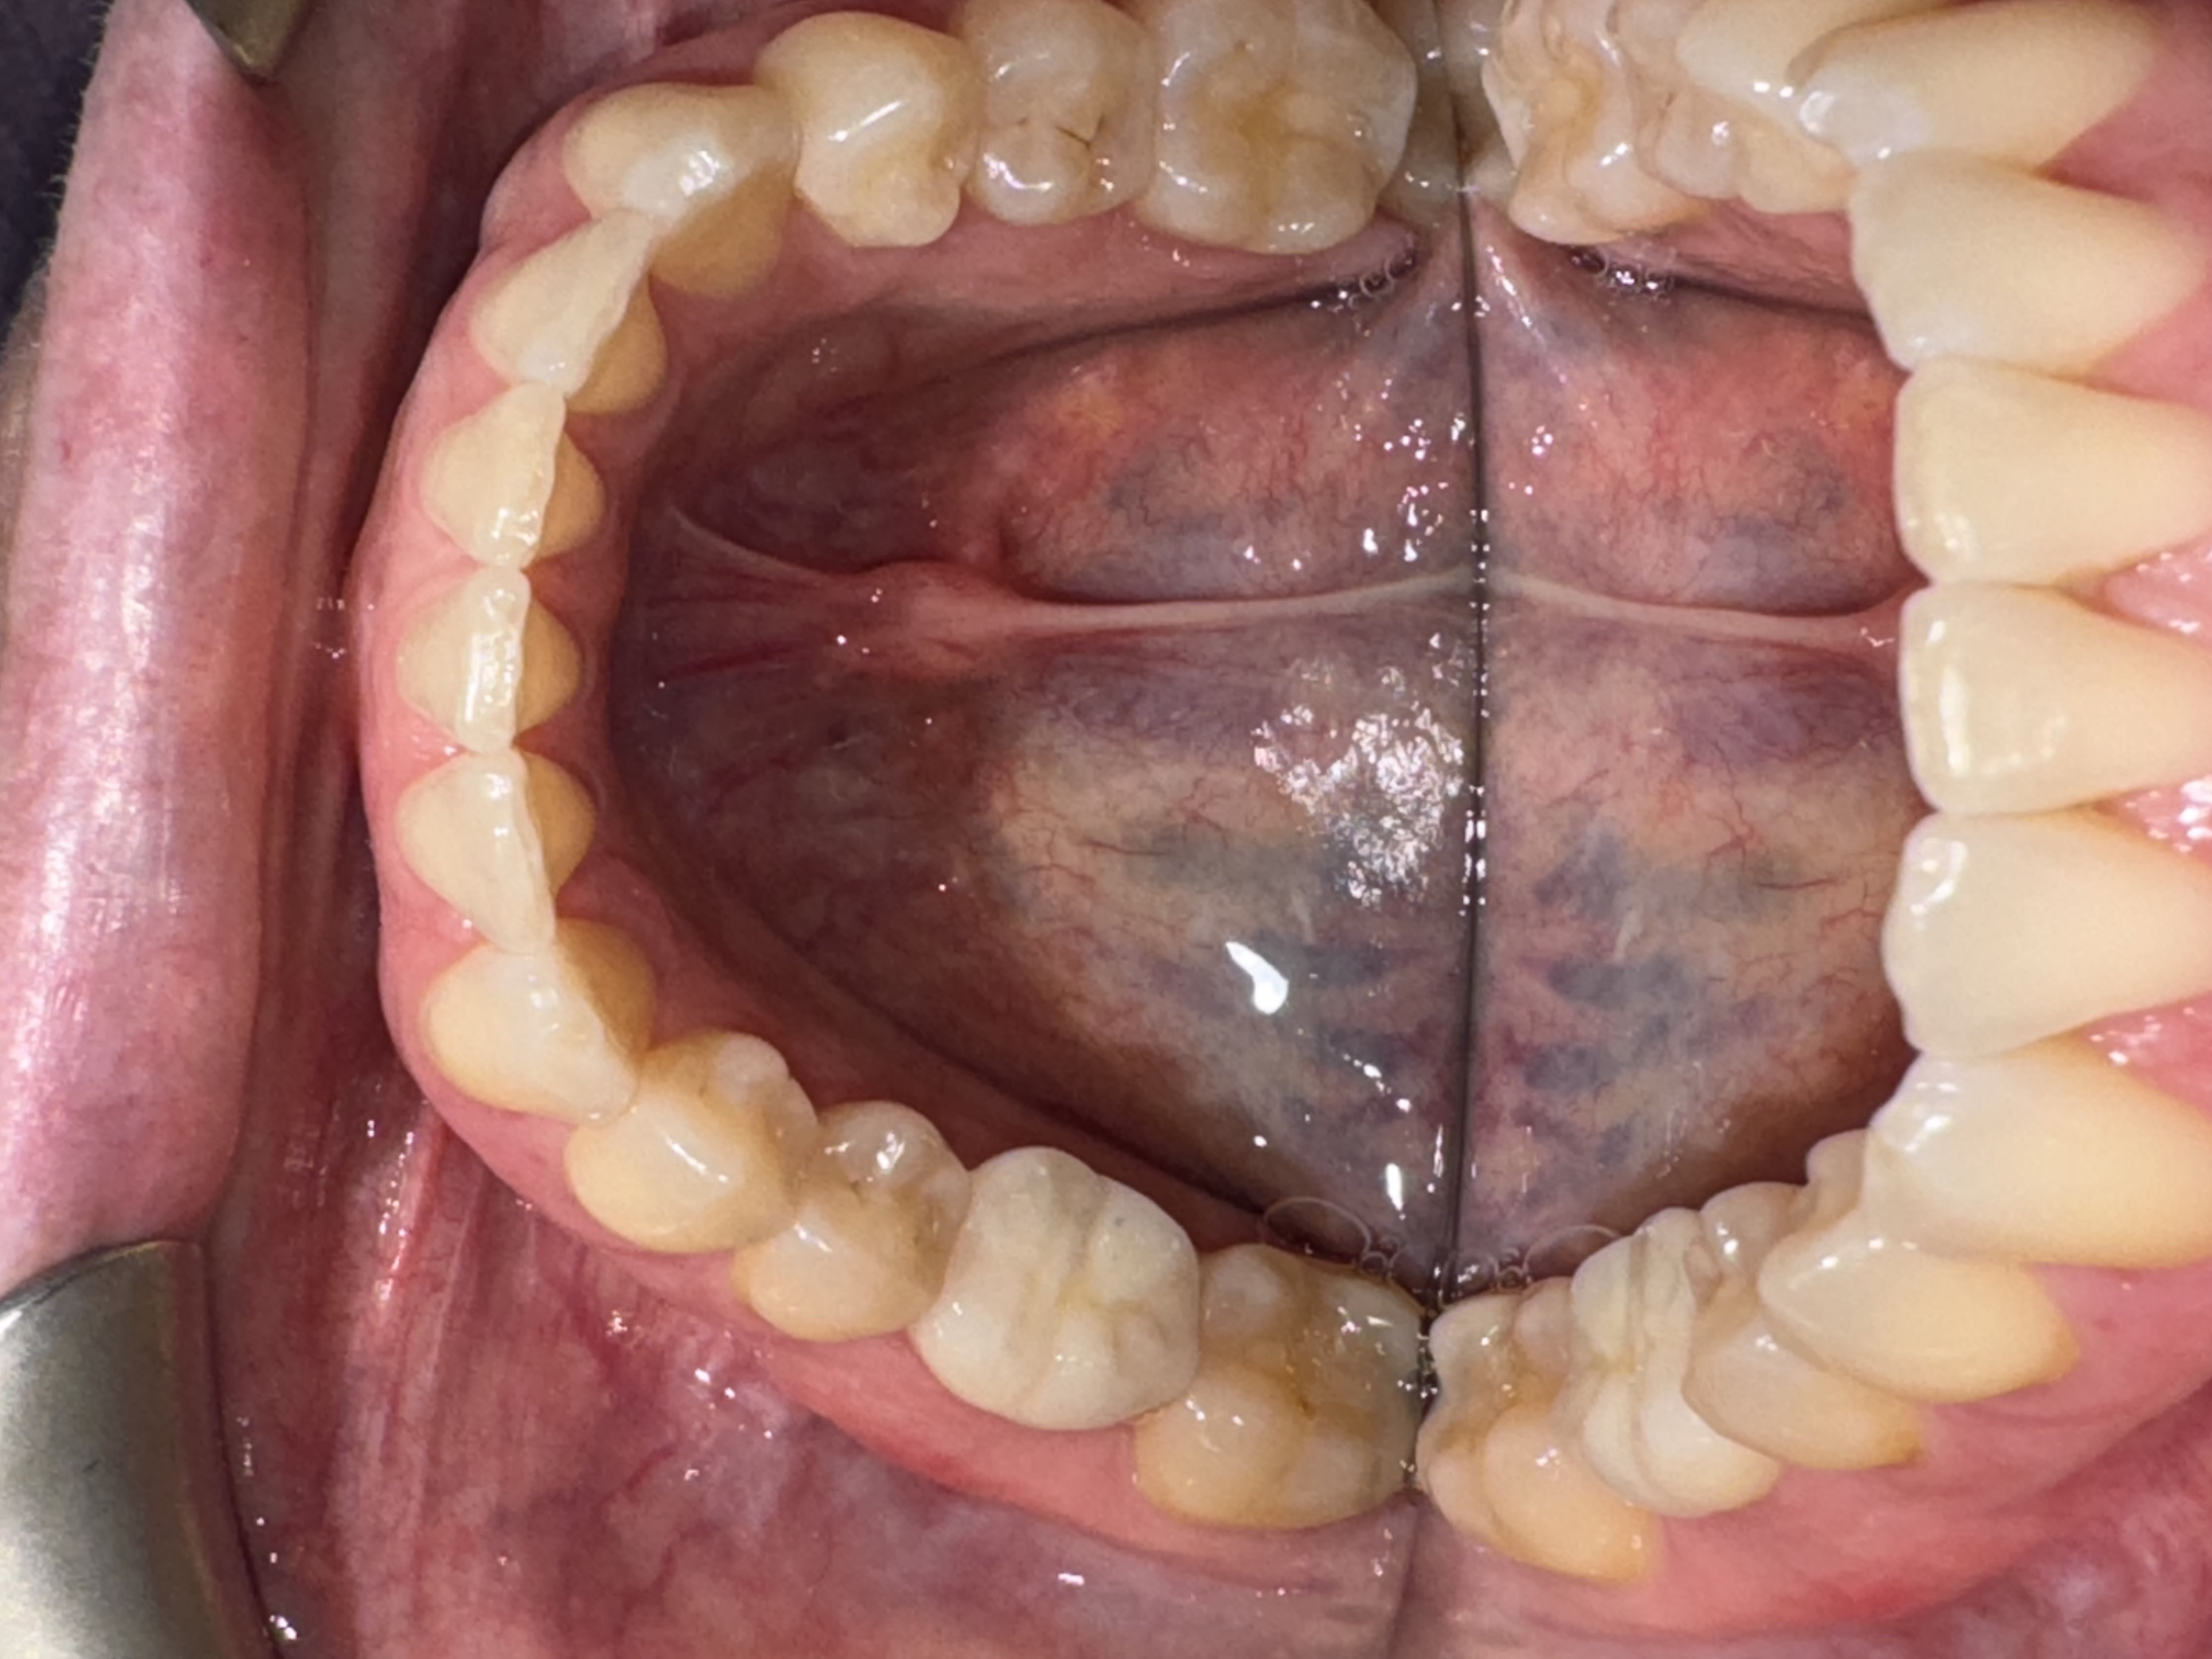

Comprehensive biological oral surgery case showing Tooth #30 extraction, guided bone regeneration, implant placement, and crown restoration using Groton Wellness’ minimally invasive, biologically supportive protocols.

This case follows Jennifer, a 47-year-old female, through the full biological treatment sequence: from extraction of Tooth #30 to guided bone regeneration, implant placement, and final crown restoration. Each step was planned with CBCT-based visualization and executed using open wound healing principles to support long-term oral and systemic wellness.

Visual Case Progression

All clinical images are shown at a consistent size for easy comparison.